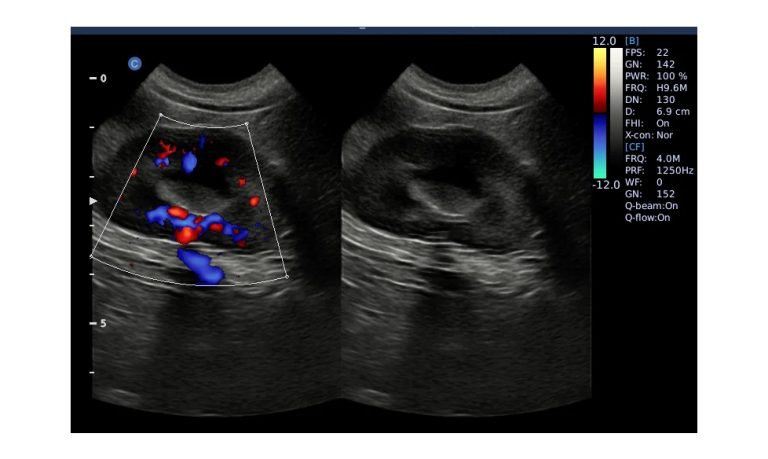

Ultrasound

Wide range of Ultrasound machines that suites a variety of applications from abdominal to rectal scans, we take in consideration how the world is moving towards mobility and mobile applications.